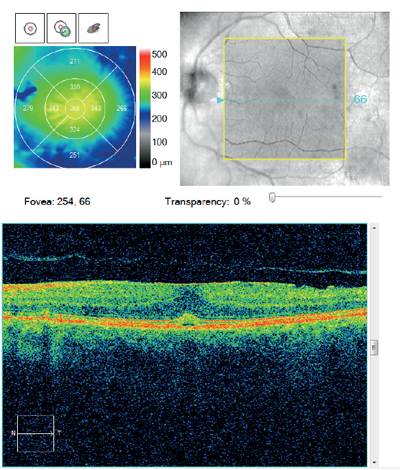

A 72-year-old gentleman presented for a follow-up appointment of a left ERM telling me that his eye felt considerably improved in terms of metamorphopsia. He had no relevant past ophthalmic history and no posterior vitreous detachment (PVD) was seen. Indeed, his BCVA showed an unusual improvement from 1.3 LogMAR at his last visit eight months before to 0.18 LogMAR when I saw him. Miraculously, on his OCT, the previous ERM (Figure 3a) had vanished (Figure 3b).

Figure 3a.

Figure 3: Macular change analysis OCT of the second patient shows a marked decrease in central retinal thickness

(b) as a result of spontaneous resolution of the ERM (a), possibly secondary to PVD.